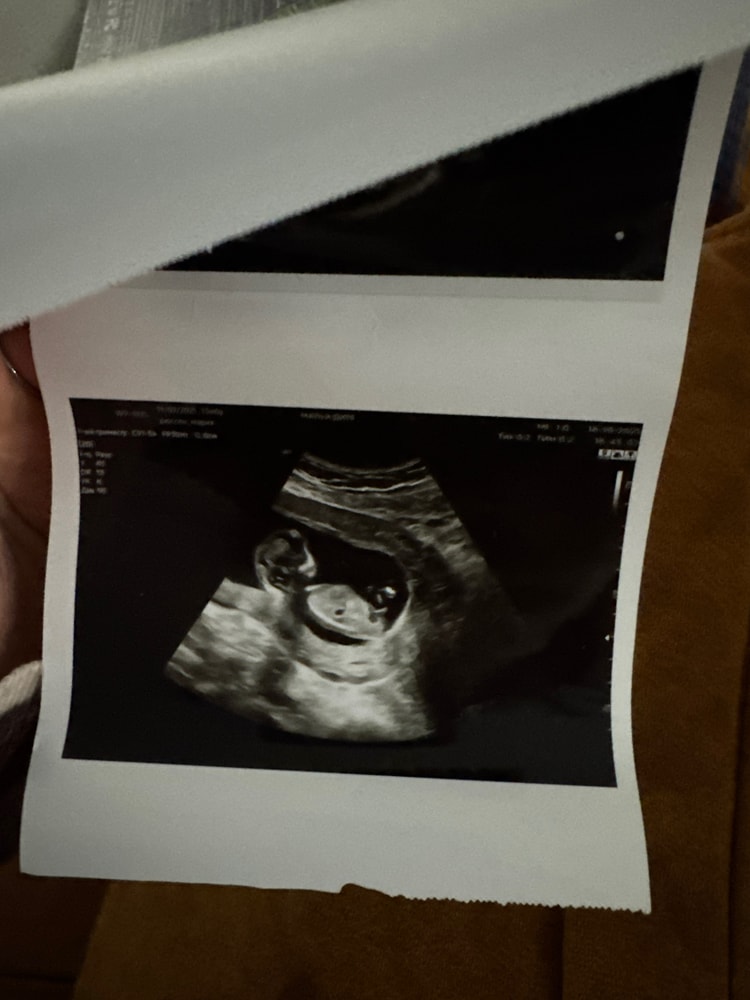

Прикрепляю свои узи, на разных узи разное положение полового бугорка, говорят мальчик, но допустим на второй фотке мне кажется половой бугорок на девочку) что думаете? Читаю разное мнение, что у кого то был прям вверх половой бугорок, а итог девочка и наоборот

Чашка утреннего кофе, нет, крайнее узи вот в 13 ровно. По первому фото врач сказала мальчик, мол половой бугорок такой)

У вас на первом фото половой бугорок, а на втором - часть ножки, полового бугорка там не видно. Мальчик у вас. Мне в 12+6 правильно пол сказали.